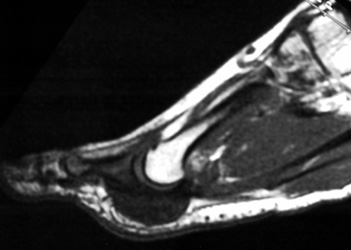

MR appearance: Typically present as persistent intermediate to low signal intensity on T1W and T2W with surrounding inflammation and post contrast enhancement. Bony erosions are also seen well.

44years old male with rapidly enlarging mass in the foot. Radiographs demonstrates soft tissue mass between the 2nd and 3rd toes,with no calcification.Well defined erosion is noted at the radial aspect of the base of proximal phalanx of 2nd toe. Mild soft tissue swelling with faint calcification is also seen at 1st MTP joint ,with small erosion medial aspect of 1st Mt head. MR demonstrates mass is isointense to hypointense on T1W, and T2W images, with minimum bone marrow edema at the base of proximal phalanx of 2nd toe. Erosion is well seen at the base of proximal phalanx of 2nd toe on T1W images.